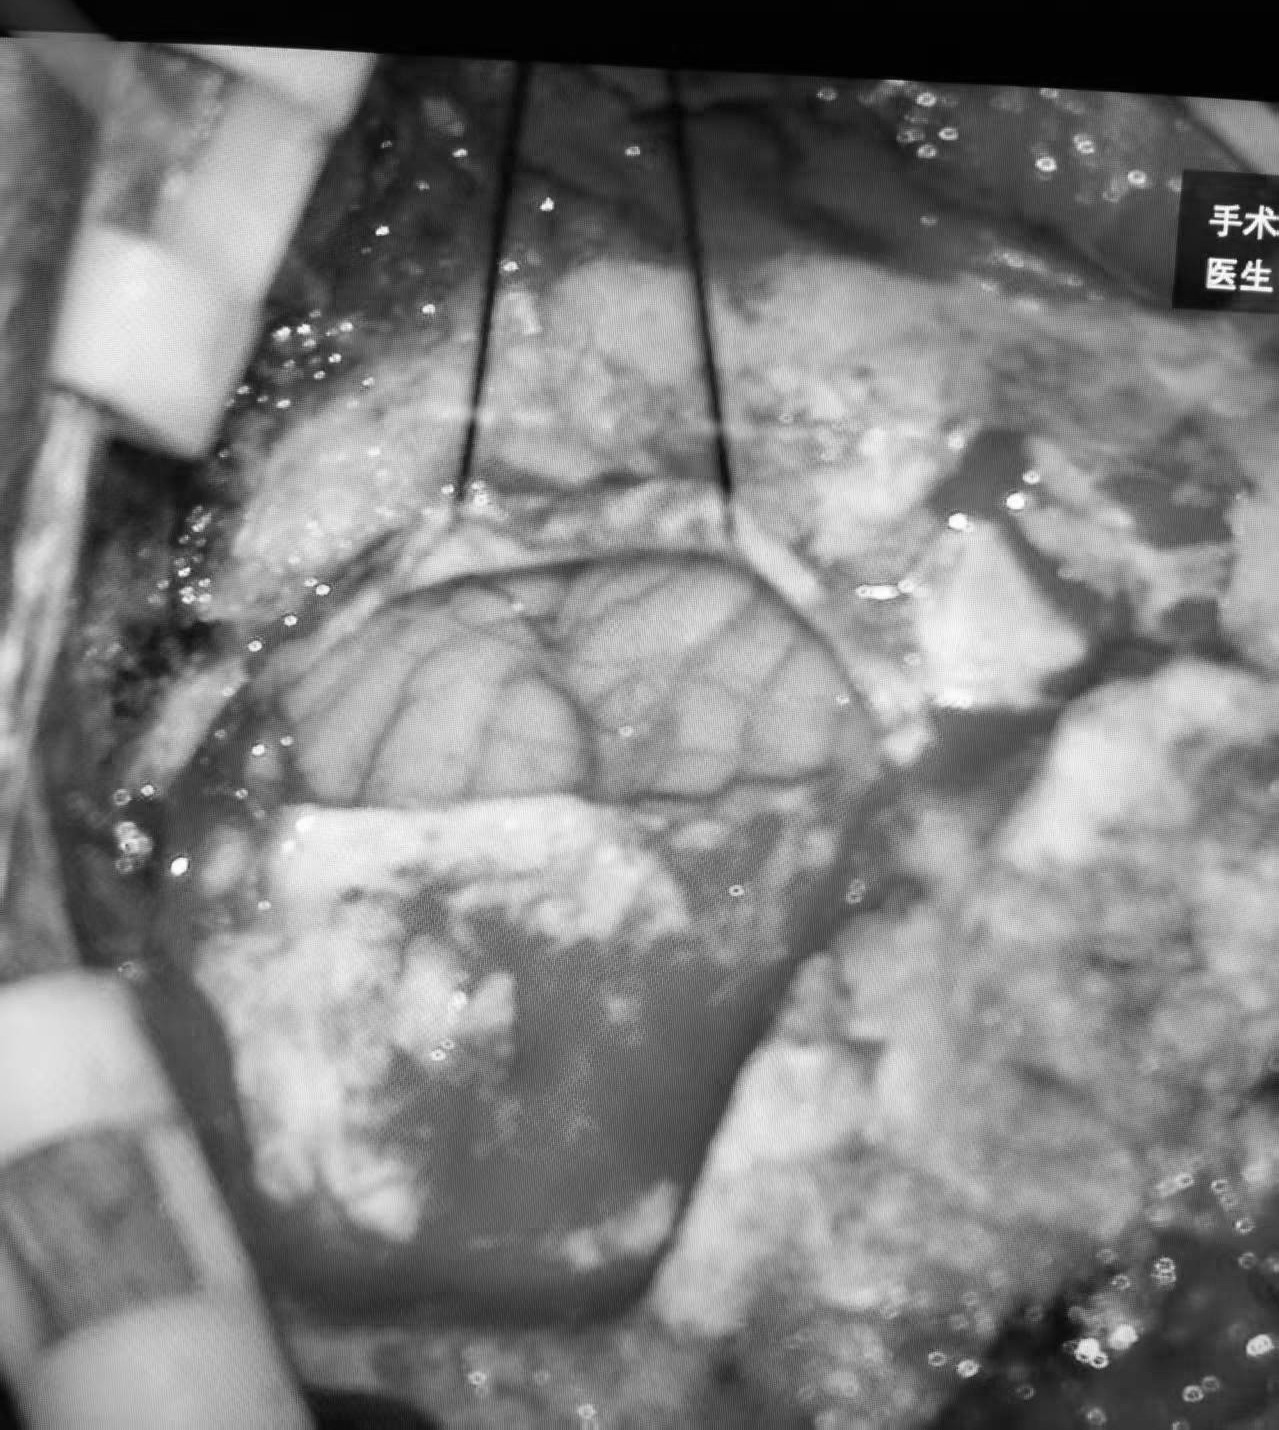

在神经电生理监测辅助下,手术团队密切配合,小心剥离血管与神经的粘连,使用Teflon棉精准垫开,彻底解除血管对神经的压迫。手术历时3小时25分,于23时50分顺利结束,术中出血约50ml,患者生命体征全程保持稳定。

术中神经电生理监测